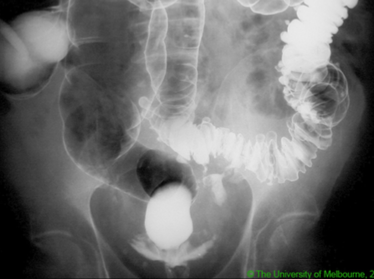

A patient with known CRC presents with progressive distension associated with obstipation and faeculent vomitus

LBO

Causes: CRC, colonic volvulus, benign stricture